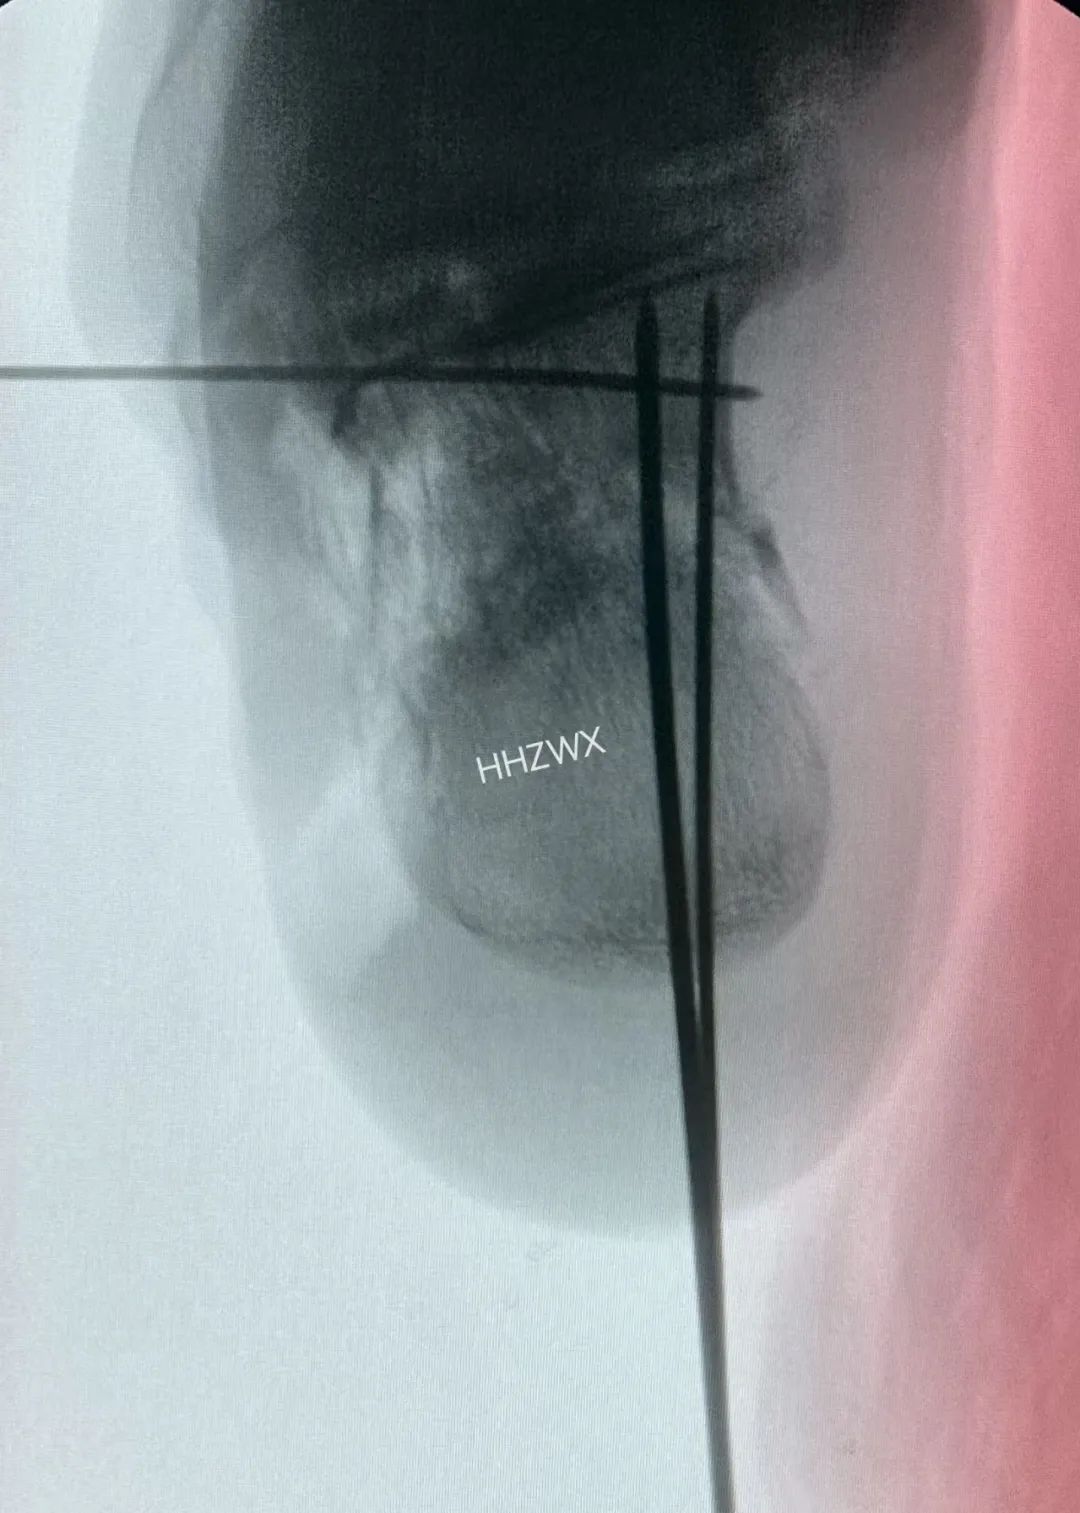

术中采取打开内侧壁后结合术中骨刀撑开合并上述手法复位内翻,然后给予克氏针固定与稳定的载距突,达到矫正并稳定内翻复位。(很多人复位位置很好,但总是固定不住,最主要的原因就是没有固定骨折块于稳定的骨折块上,固定于载距突可以很好的解决这个问题)

解决内翻之后,复位关节面,同时复位G角和舌型骨折块,辅助克氏针临时固定,可以很好的固定骨折。术中可以看到解剖复位。

这一例也是采用同样的方法,复位内翻之后,克氏针临时固定,钛针固定载距突方向复位关节面。最终解剖复位。